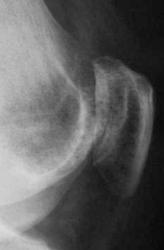

1. По всей видимости, необходимо иметь в виду феморо-пателлярный артроз. Конечно, мы не можем оценить ширину суставной щели в феморо-пателлярном суставе, так как боковой снимок сделан не в строгой боковой проекции и суставная щель, как таковая, не дифференцируется. Но можно заподозрить наличие субхондрального склероза - помечен красными стрелками и мелкие субхондральные кистовидные (точечные) просветления - желтые стрелки.

С точки зрения рентгенолога традиционной ориентации, на рентгенограммах коленного сустава из существенных изменений стоит отметить частичное обызвествление обоих менисков (больше латерального) и субхондрально расположенный линзообразной формы участок то ли остеопороза, то ли остеолиза (лучше виден в задней проекции). Артроза у старушки конечно нет!

Глядя на магниторезонансные томограммы, вижу: гвоздь проблемы именно во внутреннем мыщелке бедра. Но, чтобы интерпретировать и, по возможности объяснить картину нам отсталым, нужен иной опыт и знания. Надо звать магниторадиологов.